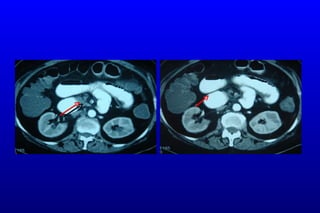

SMV Trombozu